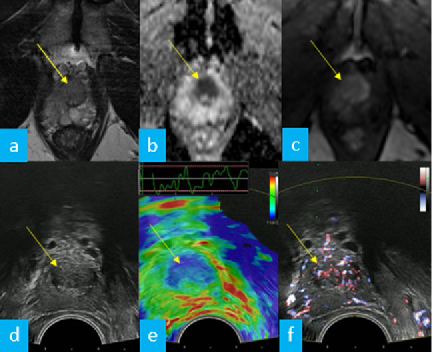

Imaging and Targeted Biopsy of the Genitourinary (GU) Tract

Friedrich Aigner

- Multiparametric ultrasound of the scrotum

- Multiparametric ultrasound of the prostate

- Multiparametric MRI of the prostate

- Fusion imaging of the GU-tract

- Fusion targeted biopsy of the prostate

The simultaneous application of structural and functional imaging techniques is described as multiparametric (MP) (Fig. 9). Studies have shown that the MP approach results in greater diagnostic accuracy (Fig. 10).

The use of fusion imaging in uroradiology improves ultrasound lesion-detection rates, shows more reliable size controls at different time points, is an alternative to in-bore biopsies (Fig. 11) and can be used for focal therapy.